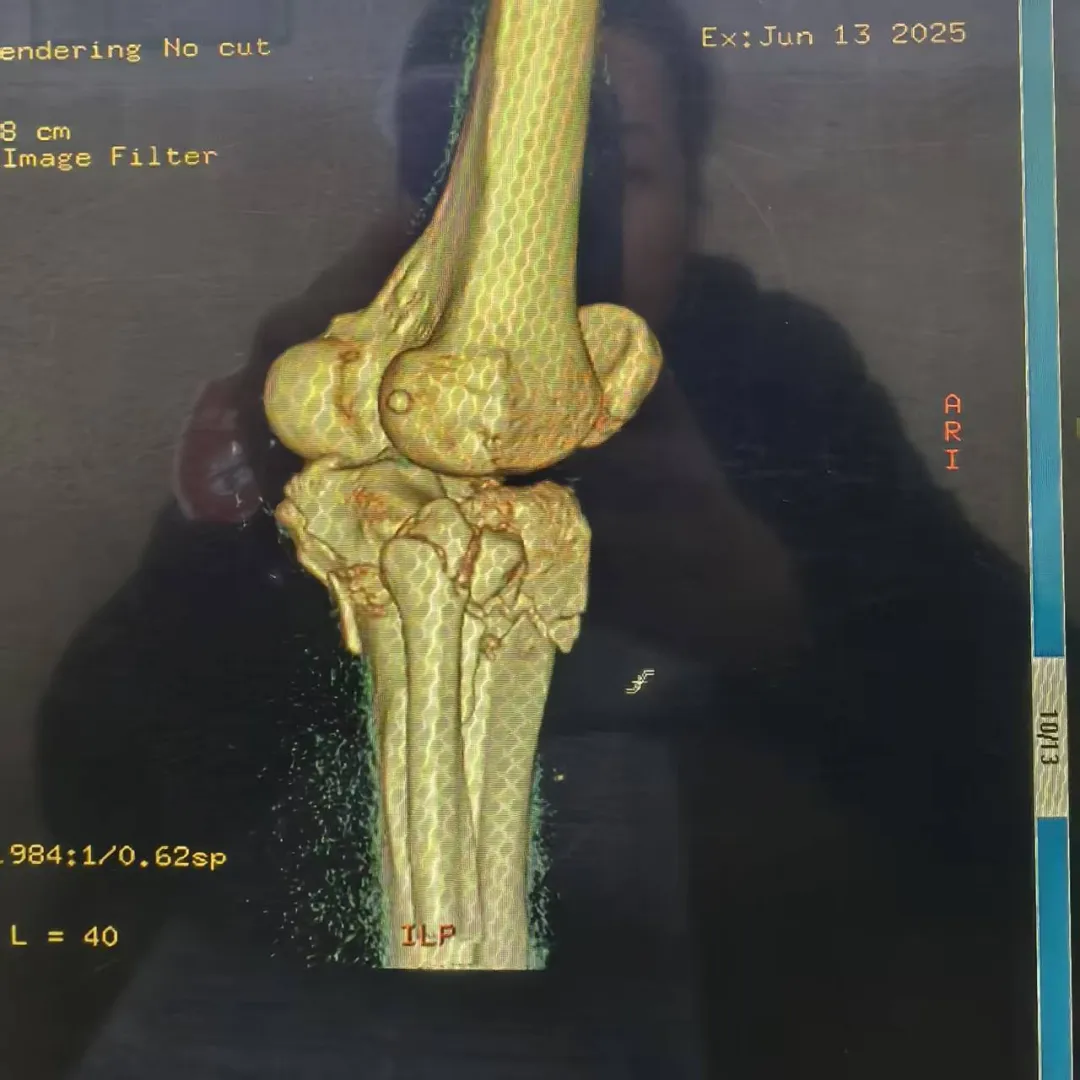

病例难点:直面手术挑战

患者石女士,34岁,因高处坠落导致右膝严重损伤。经过详细的影像学检查,诊断确认:胫骨平台后外侧粉碎性骨折(Schatzker Ⅱ型)、膝关节前、后交叉韧带及内外侧副韧带损伤、外侧半月板后角Ⅲ度损伤,内侧半月板后角Ⅰ度损伤。

骨折块粉碎严重,复位固定难度极大

面对这一复杂病例,科室医疗团队组织全科进行术前讨论,结合最新版《胫骨平台骨折诊断与治疗专家共识》,经过精密规划,最终决定采用改良Frosch后外侧入路这一先进术式。